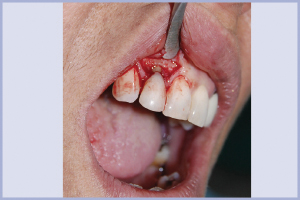

Dopo aver fatto l’anestesia plessica si è proceduto all’estrazione dell’elemento 12, nel pieno rispetto dei tessuti (Figg. 3, 4); eseguito un lembo a tutto spessore, paramarginale rispetto alle papille, si è fatta una toilette chirurgica del sito post-estrattivo e si è controllato che le pareti alveolari fossero integre (Fig. 5). A questo punto, lavorando con apparecchiatura piezoelettrica Piezosurgery, abbiamo creato un sito chirurgico più palatale rispetto al sito anatomico, per prevenire un eventuale riassorbimento della cresta alveolare vestibolare. Quindi abbiamo preparato il sito implantare, utilizzando esclusivamente le punte osteotomiche compattatrici, fino a una profondità di 14 mm dalla cresta.

- Fig. 3 – L’apertura del lembo consentiva di visualizzare la lesione apicale